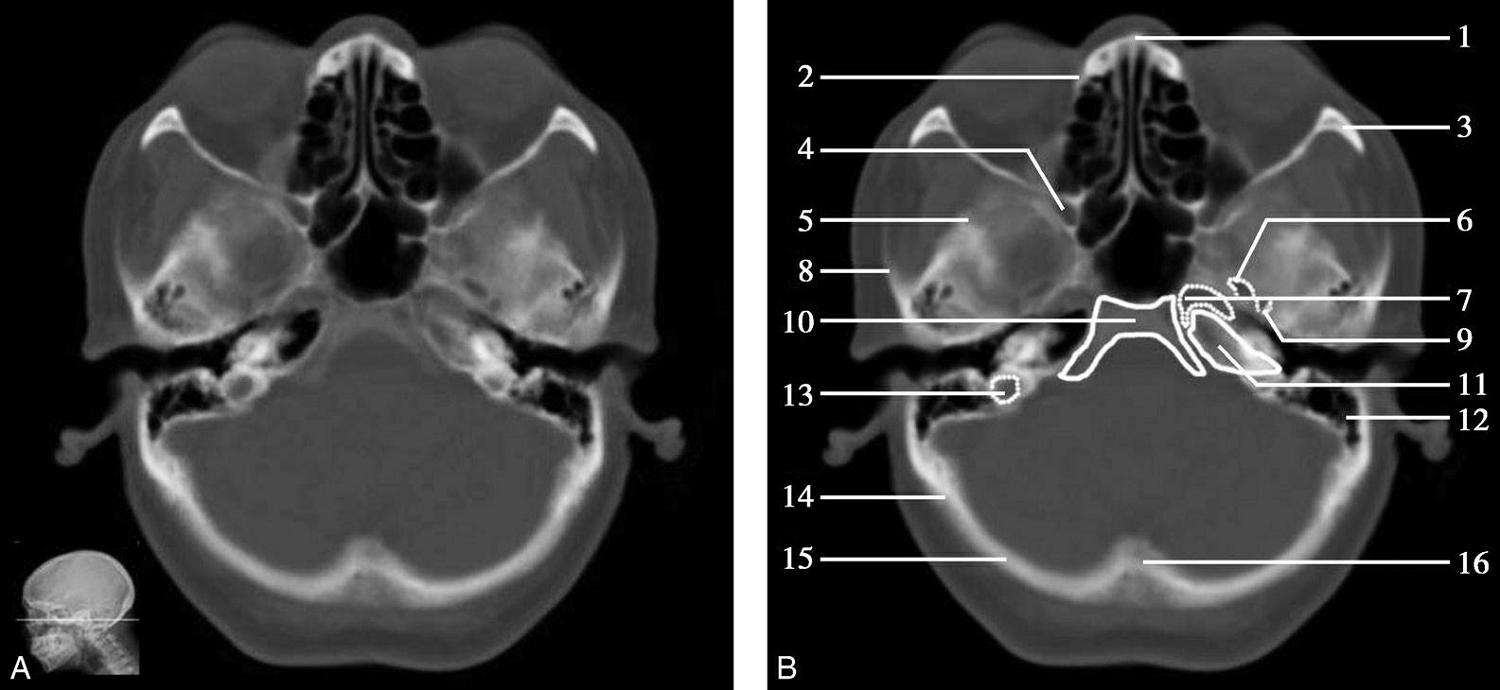

重要结构:卵圆孔、棘孔、破裂孔、斜坡、颞骨岩部、颈静脉孔(图1-2-1、图1-2-2)。

图1-2-1 颅底层面

A.横断面;B.横断面标注

1.晶状体;2.筛窦;3.颞肌;4.中颅窝底;5.外耳道;6.延髓;7.乙状窦;8.小脑半球;9.眼球;10.眼眶;11.上颌窦;12.蝶窦;13.乳突;14.耳郭;15.小脑蚓部;16.枕内隆凸

层面前部呈开口向前的“V”字形,正中为鼻中隔,向两侧依次为筛窦和眼眶,眼眶内前部为眼球,后部为眶脂体。翼腭窝位于眼眶后部,窝内含有脂肪并有上颌神经通过。层面中部为蝶骨体,蝶骨体中部可见含气蝶窦,蝶窦后方为枕骨基底部,两者呈前后关系,其上面构成斜坡。蝶窦两侧为蝶骨大翼,其后外侧缘处由前向后可见卵圆孔和棘孔,分别有下颌神经和脑膜中动脉通过。斜坡外侧、岩骨尖前方为破裂孔。蝶骨大翼与眶外侧壁的颧骨借颧弓相连,颧弓和蝶骨大翼之间有咬肌及颞肌。层面中部外侧为外耳道。颞骨岩部呈“八”字形,相互之间借破裂孔软骨、蝶岩软骨结合和岩枕软骨结合连接。岩部后外侧的乳突部内可见乳突小房,乳突部与枕骨相接。岩骨后部可见颈静脉孔,内有颈内静脉、舌咽神经、迷走神经和副神经通过。层面后部为颅后窝,其内可见延髓,延髓前方为延髓前池,内有椎动脉,后外侧为小脑半球下部,后方为第四脑室、小脑扁桃体及小脑蚓部。

破裂孔、卵圆孔、棘孔及斜坡等均为重要的解剖结构,临床常见疾病如鼻咽癌常侵犯上述结构(图1-2-3)。颈静脉孔区较常见的肿瘤为颈静脉球瘤,常伴有颈静脉孔及其邻近骨质的破坏(图1-2-4)。